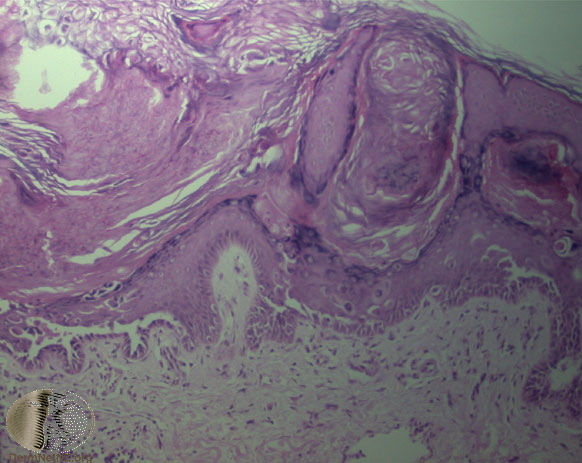

The characteristic changes in Darier’s disease include the following: (a) a peculiar form of dyskeratosis resulting in the formation of corps ronds and grains; (b) suprabasal acantholysis leading to the formation of suprabasal clefts or lacunae; and (c) irregular upward proliferation into the lacunae of papillae lined with a single layer of basal cells, so-called villi (Fig. 6-27). There are also papillomatosis, acanthosis, and hyperkeratosis. The dermis shows a chronic inflammatory infiltrate. In some cases, there is downward proliferation of epidermal cells into the dermis.

pyknotic nucleus that is surrounded by a clear halo. By virtue of size and the conspicuous halo, corps ronds stand out clearly . Peripheral to the halo lies basophilic dyskeratotic material as a shell . The nonstaining halo in some instances is partially replaced by homogeneous, eosinophilic dyskeratotic material . Compared with the corps ronds, the grains are much less conspicuous. They resemble parakeratotic cells but are somewhat larger. The nuclei of grains are elongated and often grain shaped and are surrounded by homogeneous dyskeratotic material that usually stains basophilic but may stain eosinophilic. The lacunae represent small, slitlike intraepidermal vesicles most commonly located directly above the basal layer. They contain acantholytic cells and show premature partial keratinization. Because of shrinkage, some of them are elongated, and these then appear identical with the grains in the horny layer. The villi projecting into the lacunae may be quite tortuous, so on histologic examination, some of them appear in cross section as rounded dermal structures lined by a solitary row of basal cells .